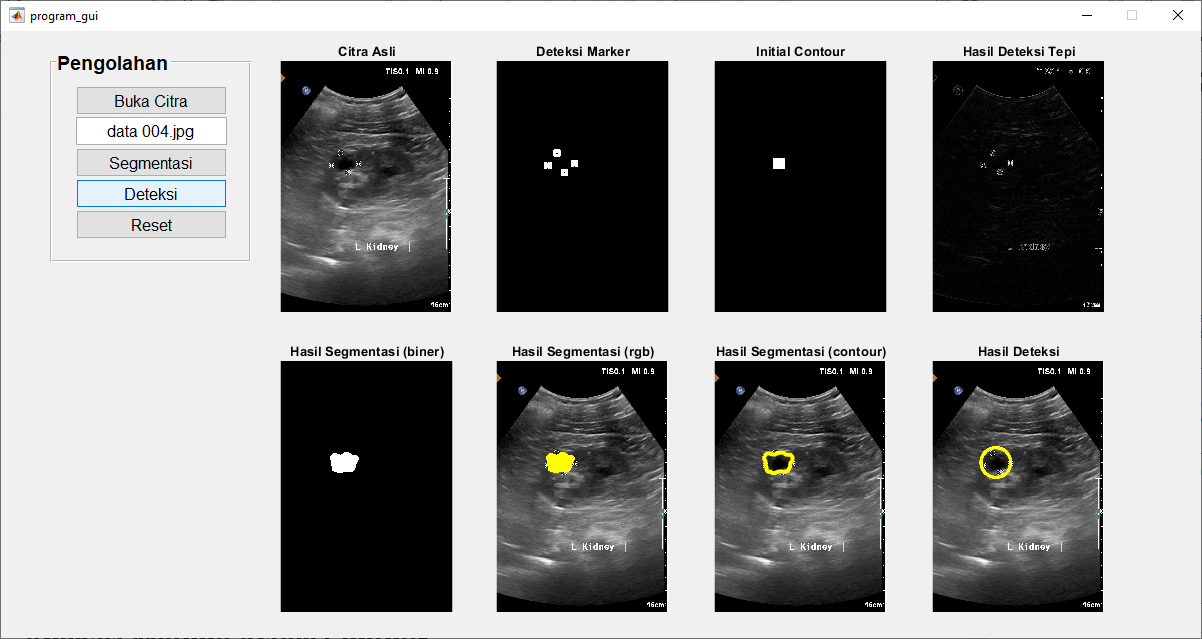

Langkah-langkah Segmentasi Citra Kista Ginjal Menggunakan Metode Active Contour

- Baca Citra Ultrasonografi

Langkah pertama dalam segmentasi citra kista ginjal adalah membaca citra ultrasonografi yang akan dianalisis. Citra ultrasonografi adalah salah satu teknik pencitraan medis yang umum digunakan untuk melihat struktur internal tubuh, termasuk organ ginjal. - Deteksi Tepi (Edge Detection)

Untuk melakukan segmentasi dengan metode active contour, kita perlu mendeteksi tepi kista ginjal terlebih dahulu. Tepi ini akan berperan sebagai “marker” atau acuan untuk inisialisasi contour. - Inisialisasi Contour

Setelah tepi kista ginjal terdeteksi, kita akan menginisialisasi contour secara otomatis menggunakan informasi dari tepi tersebut. Inisialisasi ini akan membantu snake atau contour aktif bergerak menuju tepi kista. - Active Contour

Active contour, atau snake, adalah suatu algoritma yang digunakan untuk mengubah contour secara iteratif sehingga sesuai dengan tepi objek yang ingin disegmentasi. Algoritma ini akan menyesuaikan posisi kontur berdasarkan energi yang ada dalam citra.- Energi Internal: Digunakan untuk menjaga bentuk dan elastisitas contour. Ini termasuk energi elastisitas yang mencegah contour mengalami perubahan yang terlalu besar.

- Energi Eksternal: Terkait dengan citra itu sendiri, digunakan untuk mendorong contour menuju tepi kista ginjal. Energi eksternal ini didapat dari informasi gradient citra.

- Visualisasi Hasil Segmentasi

Setelah proses active contour selesai, kita dapat memvisualisasikan hasil segmentasi. Citra hasil akan menunjukkan area kista ginjal yang telah berhasil diisolasi dari latar belakang.

Segmentasi citra kista ginjal menggunakan metode active contour berdasarkan citra ultrasonografi adalah salah satu cara yang efektif untuk mengidentifikasi dan memisahkan kista dari struktur ginjal lainnya. Metode ini melibatkan deteksi tepi, inisialisasi contour, dan proses iteratif untuk memperbaiki posisi contour agar sesuai dengan tepi kista. Hasil segmentasi ini dapat digunakan untuk diagnosis medis lebih lanjut dan perencanaan pengobatan. Dengan teknologi ini, kita dapat meningkatkan deteksi dini dan pengelolaan penyakit ginjal, termasuk kista ginjal, yang akan berdampak positif pada kesehatan pasien.